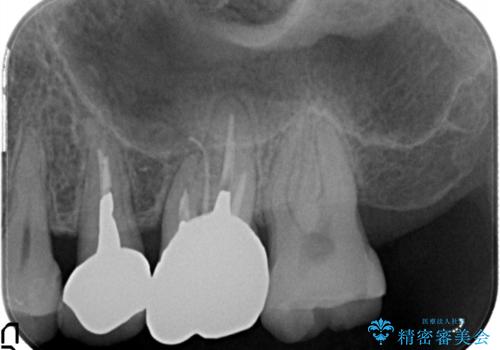

- 以前から奥歯に違和感があることを主訴に来院されました。歯肉にサイナストラクトを認めたため、再根管治療を行った後オールセラミッククラウンにて修復治療を行いました。根管治療は林先生に依頼しております。

根管治療の難易度に応じて根管治療認定医の先生を紹介させていただきます。

- 根管治療により痛みや腫れがひかない事や、術後に痛みや腫れが生じる事、治療によるファイル破折やパーフォレーションなどの偶発症、術後の歯根破折を生じる可能性もあります